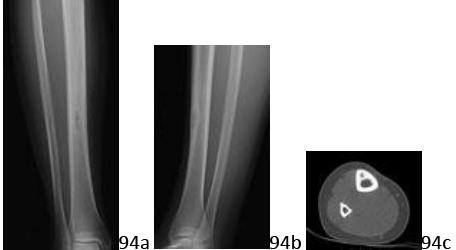

DISCUSSION: In phalanx fractures treated with a plate and open reduction and internal fixation, adhesions commonly develop between the fracture, hardware, and extensor system. This example demonstrates extrinsic tightness. The flexor tendons usually are not scarred in this type of surgical approach. The oblique retinacular ligament is near the distal interphalangeal joint and would not significantly impact the PIP joint. The intrinsics are less affected by this scarring than the extrinsics, resulting in different exam results (improved PIP motion with MP flexion). PIP joint stiffness would be constant regardless of the position of the MP joint. The Preferred Response to Questi # 11 is 2.

10. # 12a Figure 12a shows a cross section of the pelvis at the level of the greater trochanters. What structure is marked with the arrow?

1. # Adductor magnus

2. # Obturator internus

3. # Obturator externus

4. # Pectineus

5. # Adductor brevis

DISCUSSION: In Figure 12b, the arrow marks the obturator internus muscle which projects posteriorly and banks around the ischium, inserting on the posterior aspect of the proximal femur, just below the piriformis. The other structures are labeled. The obturator externus is more anterior and is seen anterior to the ischium. The adductor magnus is not seen in this image, and is more distal. The adductor longus is just starting to appear anteriorly (with the adductor brevis just posterior), and the pectineus is seen posterior and just deep to the femoral vessels. The Preferred Response to Ques# 12 is 2.